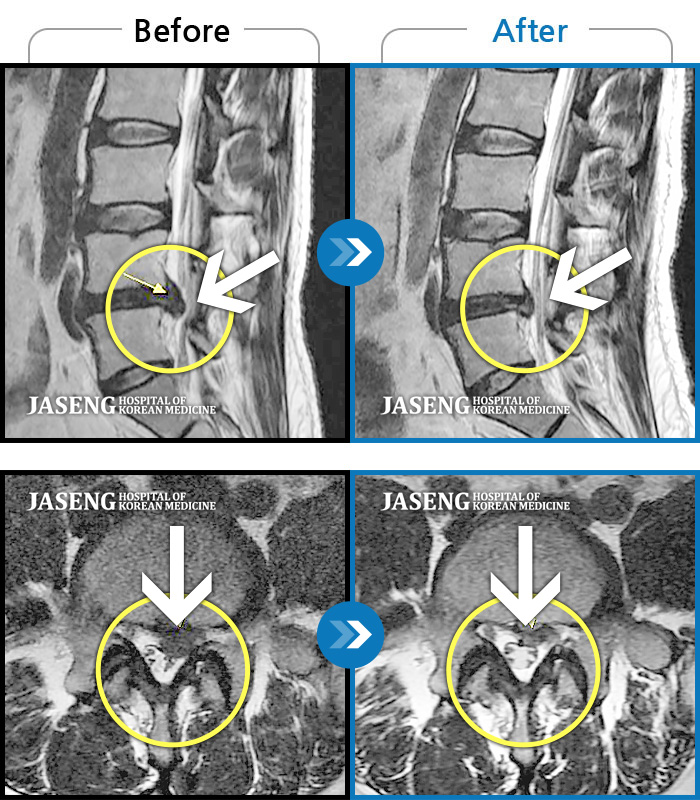

완치했다고 생각했던 허리디스크가 2년 만에 재발되서 걷는것도 많이 힘들고 일상생활이 통증에 많이 힘들었던 저를

자생에 내원하시는 데부분의 환자분들이 "허리"통증 때문에 내원을 하시는것 처럼 저또한 허리디스크, 치료를 목적으로 내원을 했는데요,

40대 초반 여성 환자인데요,, 처음 선생님 뵈었을 때에 1번,4,5번허리디스크 증상도 증상이지만,

본인 나이에 비해서 10~15년정도 퇴행이 많이 되어있어서 전체적으로 관리가 많이 필요하다고 설명해주셨구요,,